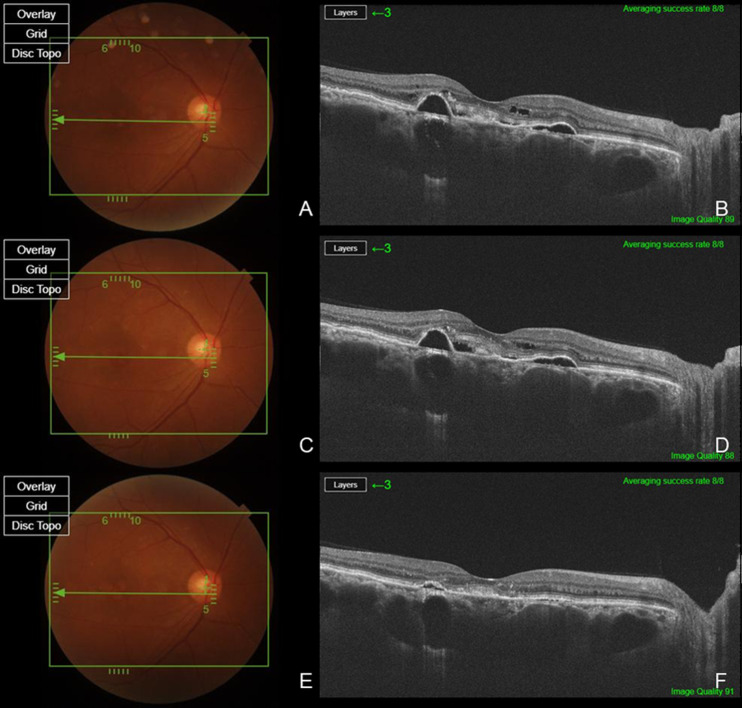

背景/目的:慢性中枢性浆液性脉络膜视网膜病变(cCSC)是一种以持续视网膜下积液(SRF)为特征的视力威胁疾病。虽然存在几种治疗方案,但其疗效各不相同,最佳管理仍不确定。这项回顾性试点研究旨在评估玻璃体内布卢珠单抗治疗无厚脉络膜样血管病(PNV)的症状性cCSC患者的疗效和安全性。方法:对15例无PNV的症状性cCSC患者的15只眼进行单次玻璃体内注射brolucizumab治疗。患者随访6个月。主要结果包括SRF的分辨率和中央亚野厚度(CST)和中央凹下脉络膜厚度(SCT)的变化。最佳矫正视力(BCVA)和眼部安全性也进行了评估。结果:15只眼中有14只眼在6个月内完全消退,占93.3%。平均CST从317.13±73.40µm显著降低至205.53±20.17µm (p < 0.001),平均SCT从475.87±107.66µm显著降低至390.13±121.67µm (p < 0.001)。BCVA改善12眼(80.0%),保持稳定3眼;然而,平均改善(logMAR 0.34±0.33至0.14±0.13)具有统计学意义(p = 0.007)。无明显的眼部不良事件报道。结论:玻璃体内注射brolucizumab可能是降低无PNV的cCSC患者SRF和脉络膜厚度的有效且安全的治疗方法。需要更大规模的对照研究来验证这些发现。

Background/Objectives: Chronic central serous chorioretinopathy (cCSC) is a vision-threatening disorder characterized by persistent subretinal fluid (SRF). While several treatment options exist, their efficacy varies, and optimal management remains uncertain. This retrospective pilot study aimed to evaluate the efficacy and safety of intravitreal brolucizumab in patients with symptomatic cCSC without pachychoroid neovasculopathy (PNV). Methods: In total, 15 eyes of 15 patients diagnosed with symptomatic cCSC without PNV were treated with a single intravitreal injection of brolucizumab. Patients were followed for six months. Primary outcomes included resolution of SRF and changes in central subfield thickness (CST) and subfoveal choroidal thickness (SCT). Best-corrected visual acuity (BCVA) and ocular safety profiles were also assessed. Results: Complete SRF resolution was observed in 14 of 15 eyes (93.3%) within six months. Mean CST significantly decreased from 317.13 ± 73.40 µm to 205.53 ± 20.17 µm (p < 0.001), and mean SCT from 475.87 ± 107.66 µm to 390.13 ± 121.67 µm (p < 0.001). BCVA improved in 12 eyes (80.0%) and remained stable in 3 eyes; however, the mean improvement (logMAR 0.34 ± 0.33 to 0.14 ± 0.13) was statistically significant (p = 0.007). No significant ocular adverse events were reported. Conclusions: Intravitreal brolucizumab may be an effective and safe treatment for reducing SRF and choroidal thickness in patients with cCSC without PNV. Larger, controlled studies are needed to validate these findings.